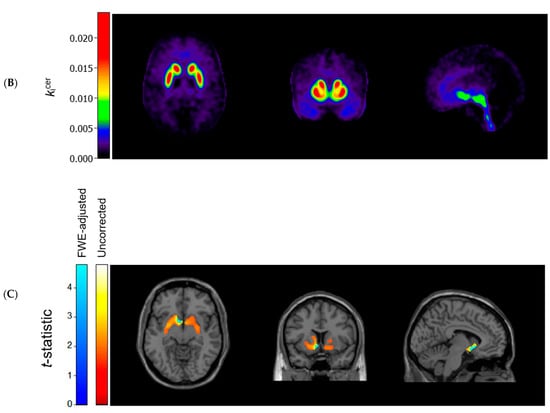

Figure 1 (panels A and B) shows the average kicer for ASD and control participants in voxels throughout the brain. In striatal as well as extrastriatal regions, we found no statistically significant differences in the kicer values between ASD and controls, and in neither sample did we observe significant associations between the kicer values and the AQ total or social interaction subscale scores. These results were similar, regardless of whether we adjusted for confounders, applied varying kicer thresholds, used unsmoothed data or data smoothed with a 4 FWHM Gaussian filter, or examined the results for the two PET/CT scanners separately. We did observe, in accordance with the ROI analysis, that kicer values in a small cluster of voxels in the left nucleus accumbens, significantly negatively correlated with the AQ attention to detail subscale in the ASD sample (and not in controls) (Figure 1C). At more lenient p-value thresholds, this association extended to larger parts of the striatum bilaterally.

Figure 1.

Axial (left), coronal (middle), and sagittal (right) view of the mean cerebral [18F]-FDOPA uptake (kicer min−1; unadjusted and unsmoothed) in (A) adults with autism spectrum disorder (n = 44) and (B) controls (n = 22). Panel (C) shows statistically significant negative associations between scores on the autism spectrum quotient attention to detail subscale and kicer values in autistic adults, overlaid on a single subject T1-weighted MRI scan, when family-wise error (FWE) rate-adjusted or unadjusted p-values of 0.05 are used (8 mm smoothing, threshold of kicer ≥ 0.005).